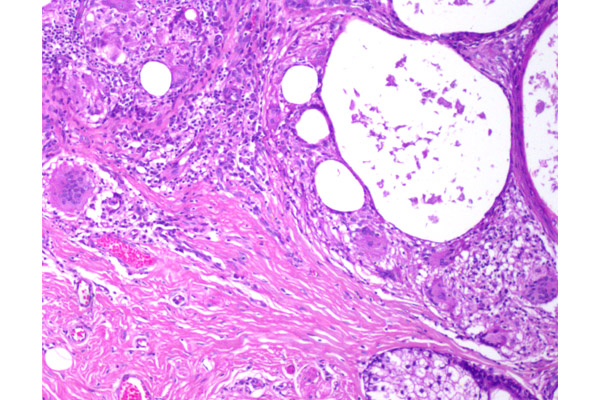

El granuloma está ocupado en casi su totalidad por una gran acumulación de grasa, que se observa como un espacio ópticamente vacío.

En algunas oportunidades, la grasa no se observa fácilmente. Sin embargo, en este campo se reconocen células gigantes de tipo cuerpo extraño, caracterizadas por la distribución al azar de sus núcleos.

En el citoplasma de las células gigantes, y libre en el tejido se puede observar acumulación de lípidos.

Algunas células gigantes pueden contener gotas de grasa y otras estar desprovistas de esta.